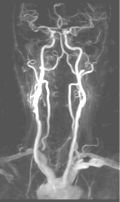

CE-MRA of the aortic arch and great vessels (left) into the brain, renal arteries (top), selective carotid bifurcation (top right) showing ICA/ECA stenosis, and 3-section run-off (very right) showing multiple stenoses, including long-segment bilateral SFA stenoses.